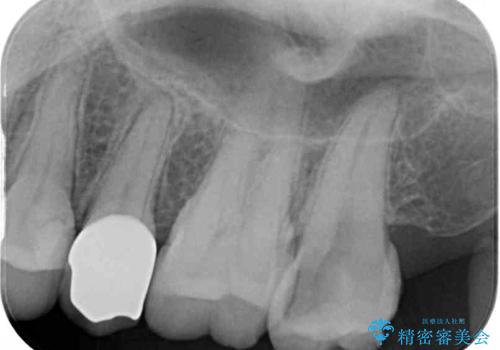

診査をしたところ、レントゲン写真よりとても大きなむし歯があることが分かりました。

虫歯が歯髄腔(神経の部屋)に達している可能性が非常に高かったため、炎症を起こしている神経組織を部分的に切除し、歯根部分の神経組織を保存する治療法が望ましいと考えられました。